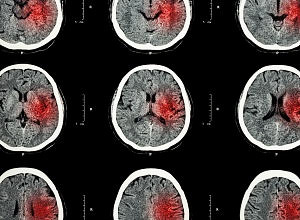

The capacity of the human brain to recover and rewire itself peaks around two weeks after a stroke and diminishes over time, found a small international study.

The researchers scanned the brains of stroke survivors as they recovered over 12 months. They found that in the initial days following an ischemic stroke (caused by a blocked artery to the brain), the brain has a greater capacity to modify its neural connections and its plasticity is increased.

The researchers used continuous transcranial magnetic stimulation (cTBS) to repetitively activate different hemispheres of the motor cortex to measure brain plasticity.

The Adelaide laboratory tested the stroke damaged motor cortex, which is the main area that controls movement. The London laboratory tested the non-stroke damaged hemisphere which is also important to help recovery.

"Our assessments showed that plasticity was strongest around two weeks after stroke in the non-damaged motor cortex. Contrary to what we expected, there was no change in the damaged hemisphere in response to cTBS."